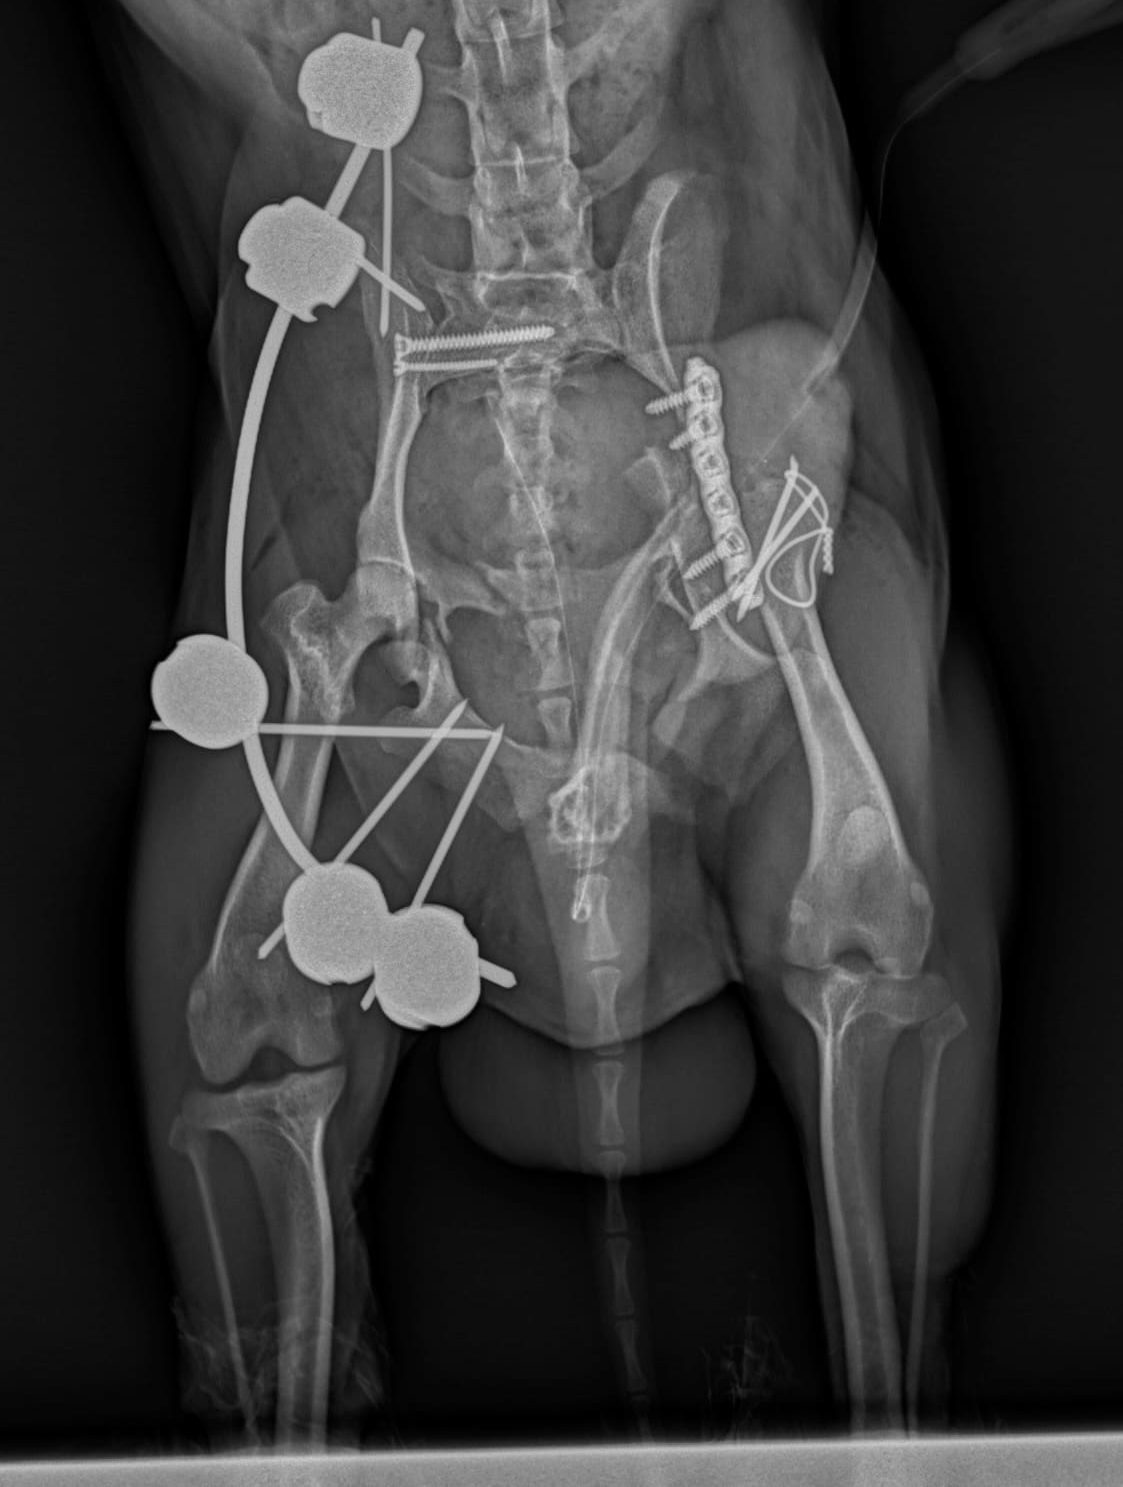

Hoy queremos contaros la historia de Nano, un pequeño Chihuahua de apenas 2 kg y 5 años de edad. Nano sufrió un grave atropello de

Hoy queremos contaros la historia de Pitu, un pequeño de apenas 3 kg y 13 años de edad. Pitu es un chihuahua que, a pesar

“Copine” es una Beagle de 5 años de edad y 18 kg de peso, que se presentó en nuestra consulta con historia de cojera severa